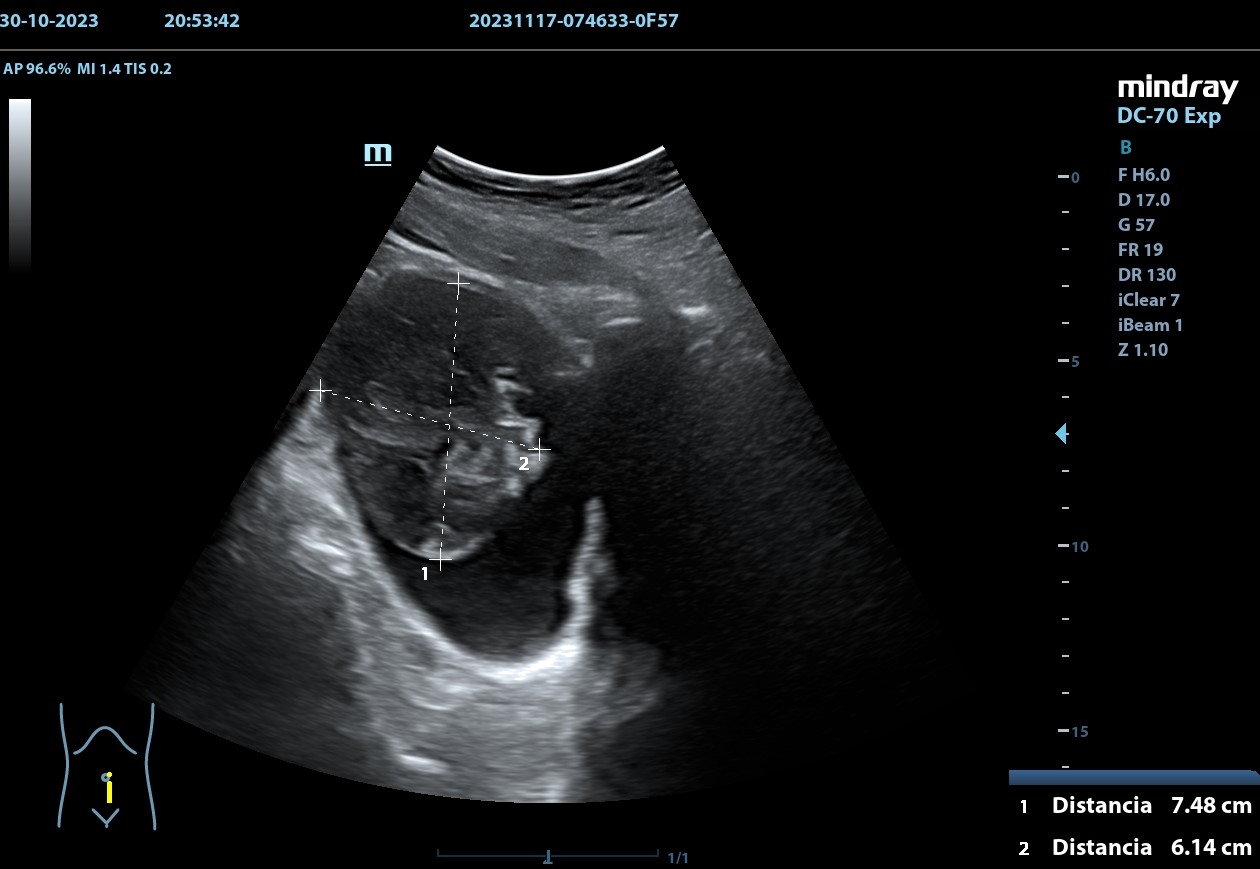

Se realiza, en consulta, una ecografía de las vías urinarias (POCUS), apreciando una lesión excrecente, pediculada, de 7,48 x 6,14 cm, que afecta a la pared izquierda y superior de la vejiga. Doppler negativo. No apreciándose jets ureterales. Riñón izquierdo de 11cm, y derecho de 9.27 cm, sin signos de dilatación de las pelvis renales que sugieran hidronefrosis.